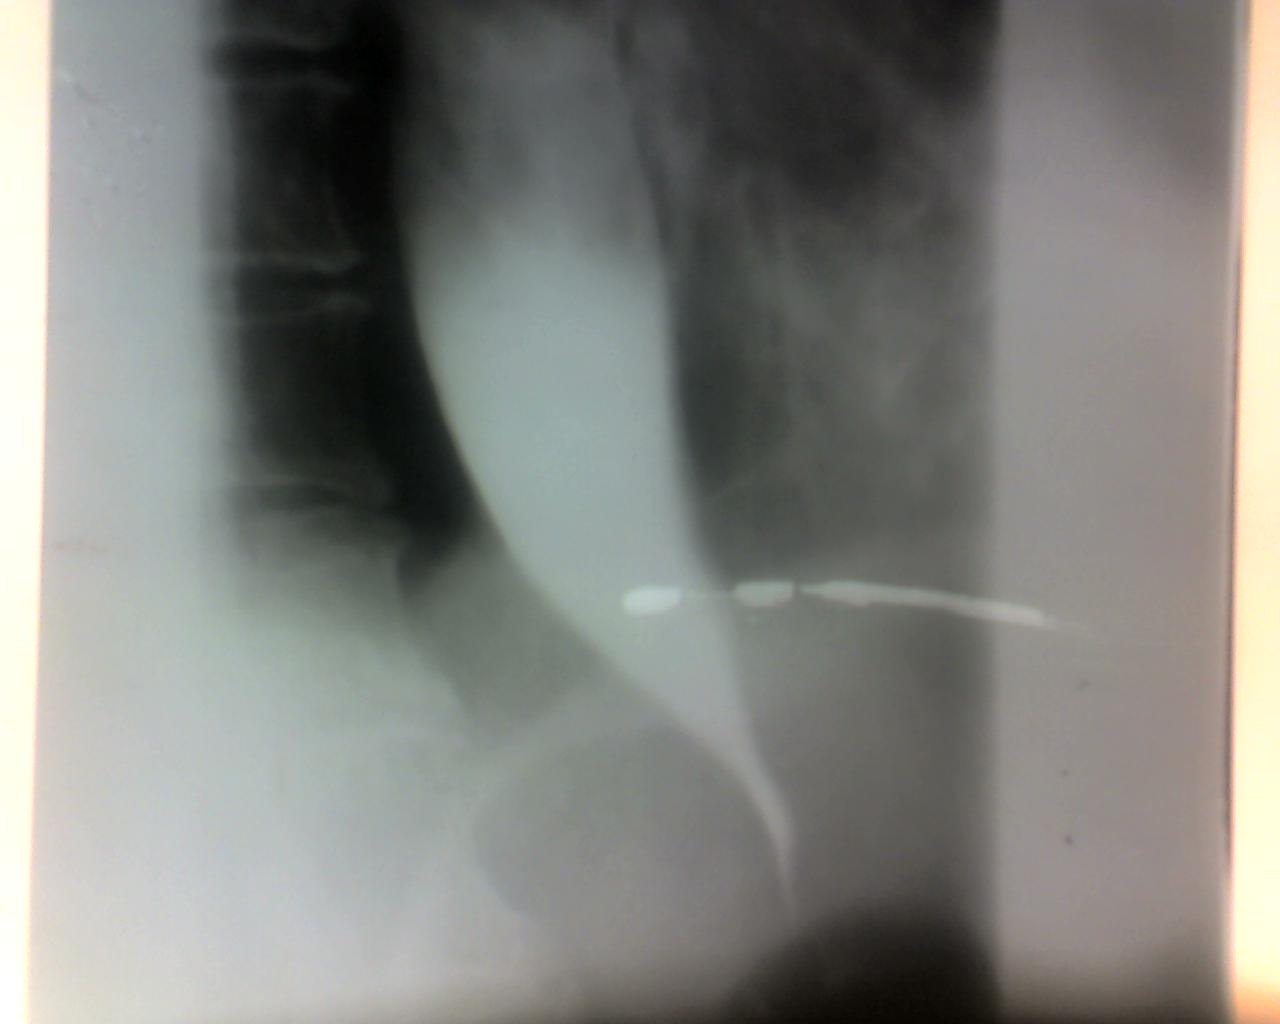

男,77岁,主因吞咽困难七天来院就诊.

食管下段漏斗样改变,边缘锐利,不象恶性原因造成的。考虑贲门失迟缓症,又称贲门痉挛、巨食管、是由食管神经肌肉功能障碍所致的疾病,其主要特征是食管缺乏蠕动,食管下端括约肌(les)高压和对吞咽动作的松弛反应减弱。临床表现为咽下困难、食物反流和下端胸骨后不适或疼痛。。食管扩张分度:轻度扩张(直径<3.5cm)

中度扩张(直径3.6~ 6.0 cm )重度扩张(直径大于6.1

cm

图像太少,说不好。食道下端及贲门部呈“鸟嘴”状改变,考虑贲门失驰缓没问题,但年龄大,贲门胃底占位可以排除吗?

食道下端及贲门部呈“胡萝卜根”状改变,考虑贲门失驰缓没问题

鸟嘴样改变  考虑食管贲门失弛缓征

食道下段及贲门狭窄呈典型萝卜根状,粘膜无破坏,中上段食道明显扩张,胃底无改变,是典型的贲门失弛缓症。